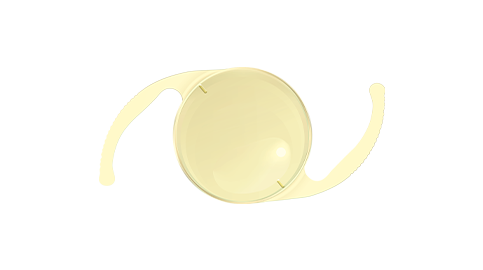

Eyebright Medical Technology (Beijing) Co., Ltd. (“Eyebright Medical”; SH Stock Code: 688050) is a National High-tech Enterprise and state-level technologically advanced "Little Giant" enterprises, located in Zhongguancun Science and Technology Park, Beijing, China. The Company is an innovation-driven ophthalmic medical device manufacturer. Its balanced product portfolio spans three major areas of the ophthalmic field: surgical treatment, myopia management, as well as consumer vision care. Anchored by its three core product categories - intraocular lenses, orthokeratology lenses, and soft contact lenses - the company has strategically expanded its product pipeline to cover the full life cycle of eye health solutions. Eyebright Medical is striding into a world-leading medical enterprise on behalf of China’s "Intelligent Manufacturing" power.